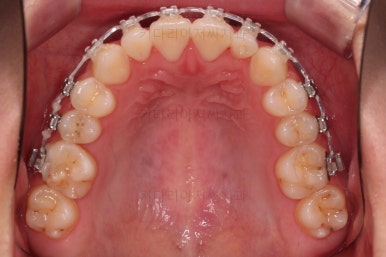

5. 마무리

유지장치를 잘 부착하고요.

왜소치가 있어서 중앙선과 교합을 맞추는데 약간의 애로사항이 있었지만 최대한 잘 마무리를 하였습니다.

앞니 각도, 가지런한 느낌, 덧니 등 모든 점이 다 개선되었네요.

부산옥니교정 전후를 비교해 볼게요.

입안의 모습에서도 모든게 다 좋아졌고요.

웃는 모습과도 매우 조화롭게 치열이 가지런해졌네요.

앞니 각도가 개선되면서 웃을 때 보이는 치열도 가득차 보이고 환해보이고요.

다물었을 때의 옆모습도 약간 오목하던 입매가 볼륨감이 생기면서 훨씬 예뻐졌습니다.